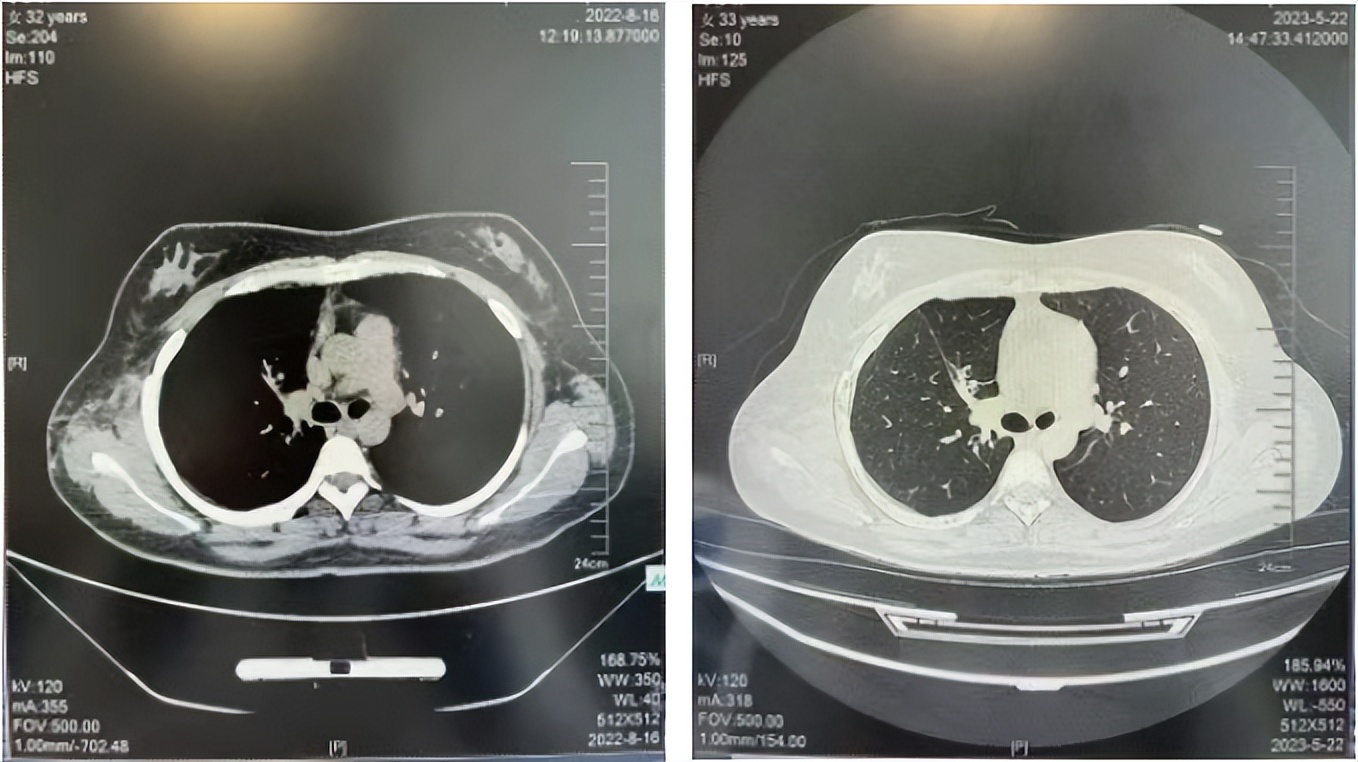

2016年1月复查CT提示支气管截断可见新发小结节,一线治疗采用培美曲塞+DDP方案化疗4周期(培美曲塞3.36,DDP 480mg)。化疗后复查胸部CT:右肺见不规则结节样影,最大层面大小约19mm*8mm,较前比较明显增大,疗效评估PD。2017.3-2017.4予单药多西他赛化疗3周期,疗效评估SD。2018年5月末复查CT提示结节较前增大,评效为PD,2018年6-10月予多西他赛+CBP化疗4周期,疗效评估SD。2022年5月患者出现活动后气短,复查胸部CT示右肺膨胀不良;右侧胸腔积液增多。胸腔积液包埋病理示符合肺腺癌细胞。行NGS基因检测:EML4:exon13-ALK:exon20融合。PD-L1(克隆号22C3)TPS<1%。

临床诊断:右肺上叶恶性肿瘤rT0N0M1a IVA期(第9版分期);恶性胸腔积液。

诊疗经过:2022年5月始口服克唑替尼3个月,出现肝功能异常(DILI 2级伴临床症状),改用恩沙替尼靶向治疗至今,目前评效为维持PR。恩沙替尼应用期间出现轻度肝功能异常(DILI 1级),对症处理后好转。截止目前PFS 33个月。

2022.08

2023.05

2024.12